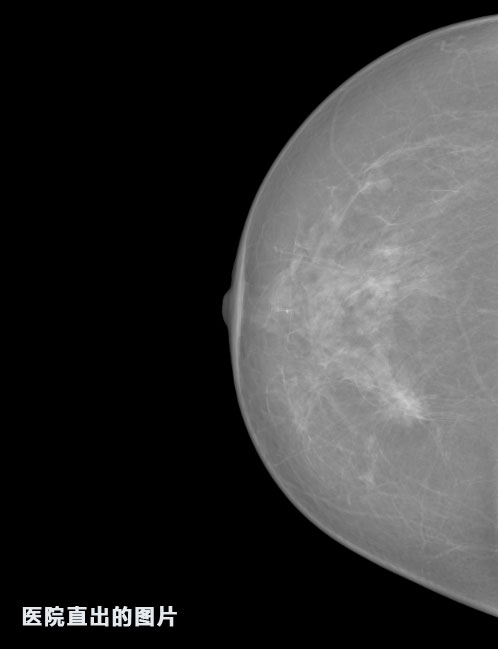

英特健康A(chǔ)I深度學(xué)習(xí)醫(yī)療圖像識(shí)別系統(tǒng)案例_乳腺

01.jpg

02.jpg